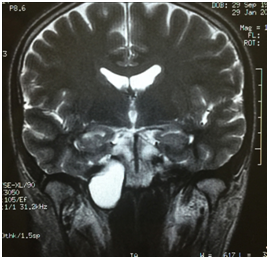

A 43years old man presented with 6month history of intermittent right hemicranial headache and ipsilateral conductive hearingloss. The patient had no historyof head trauma. The MRI demonstrated a large and expansile right petrous apex lesion hyper intense on both T1- and T2-weighted scans, without diffusion restriction or internal contrast enhancement. The CT scan showed and expansile and lyticlesion with surrounded bony erosion (Figures 1-4).

Figure 1 A large expansile lesion is noted in the right petrous apex, hyper intense on both T1- and T2-weighted scans, without diffusion restriction or internal contrast enhancement.